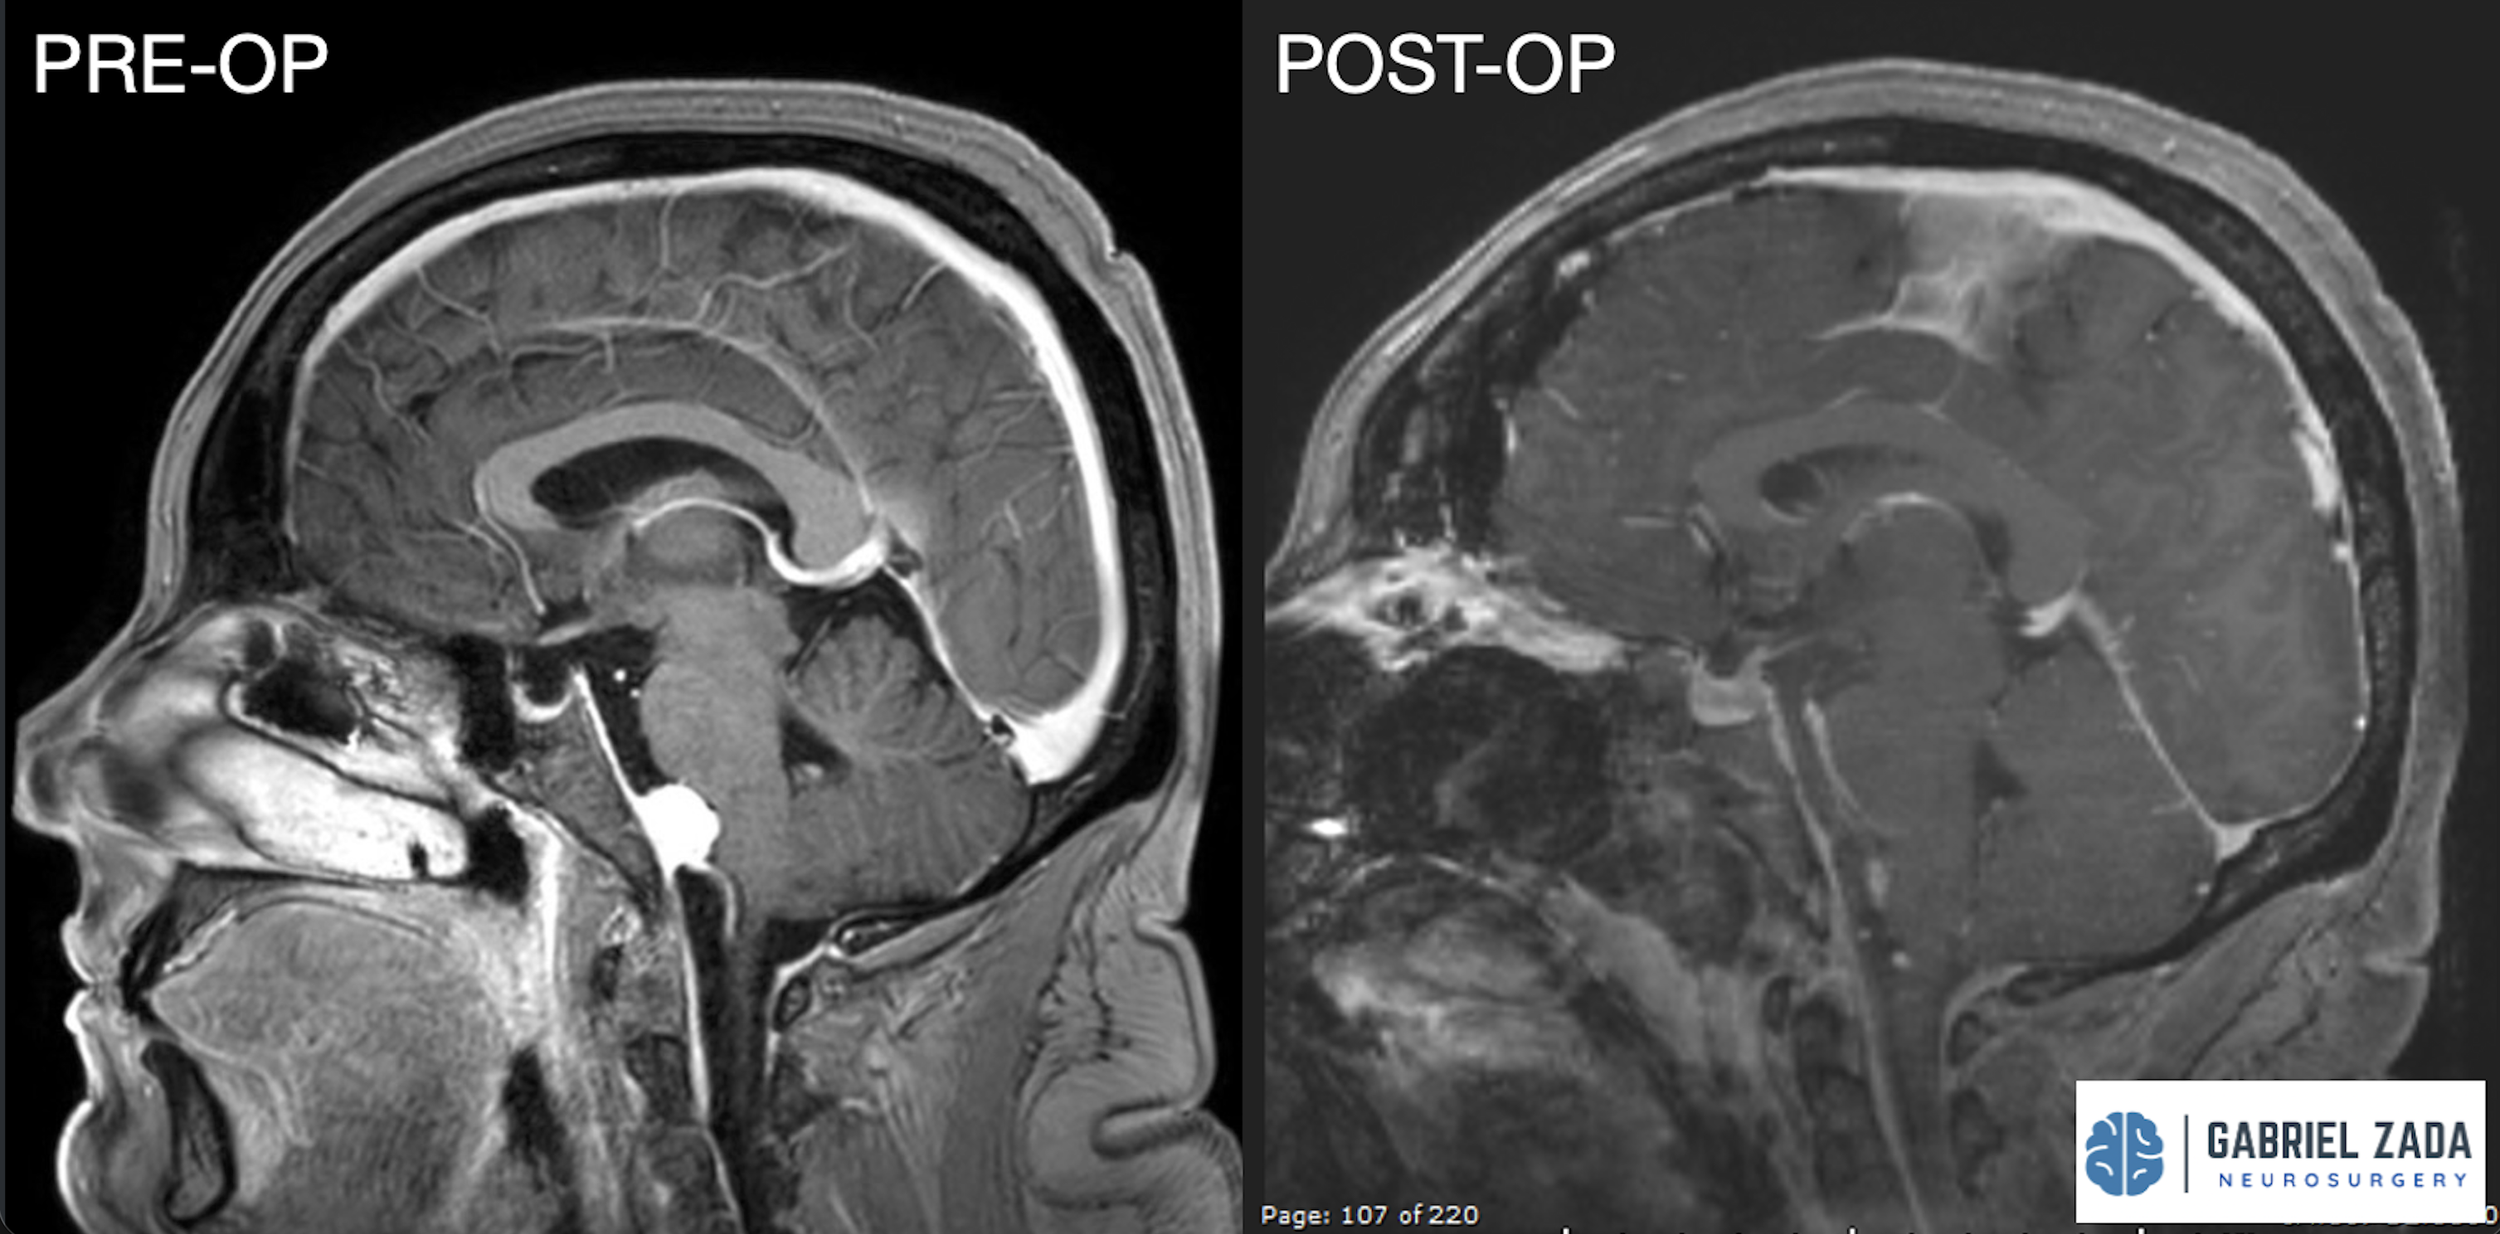

Explore this comprehensive gallery featuring pre‑ and post‑operative imaging of patients with skull‑base tumors treated by Gabriel Zada, MD, MS, FAANS, FACS. These cases highlight Dr. Zada’s expertise in advanced neurosurgical techniques and outcomes.

*Representative cases shown for educational purposes. All images de-identified. Individual results vary.